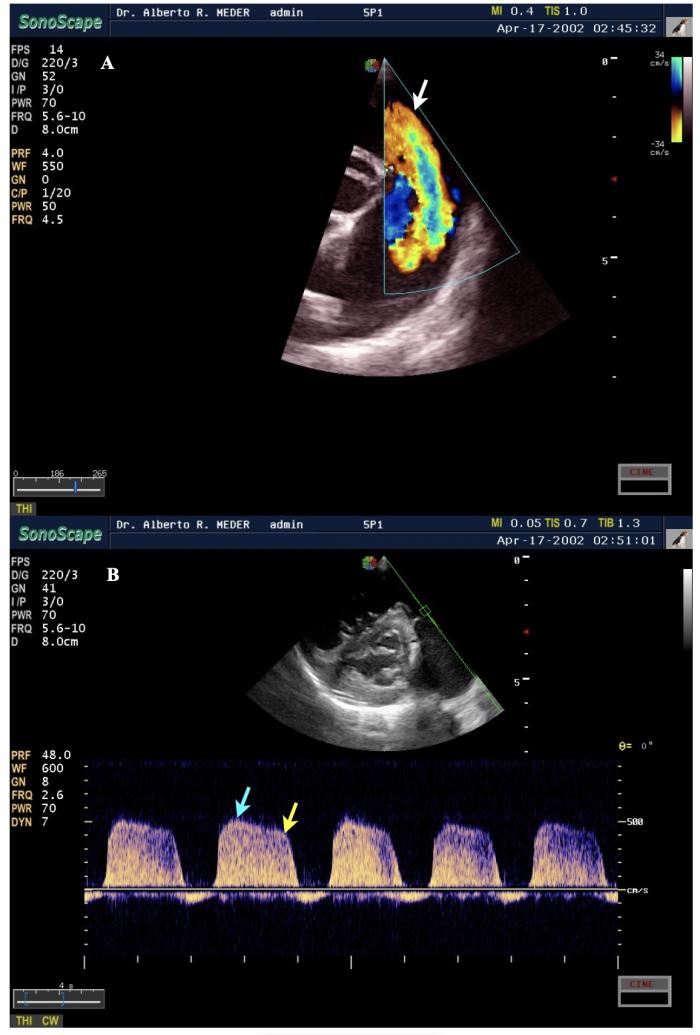

Por otro lado, la exploración Doppler espectral continuo del tracto de salida del ventrículo derecho muestra flujo pulmonar tipo II o III, con velocidades variables (generalmente >1.3 m/s) e insuficiencia pulmonar en casos graves, parámetro utilizado como estimación indirecta de la presión arterial pulmonar diastólica, con pico de velocidad temprano >2.5 m/s12,13,14(Figura5). Es importante considerar las limitaciones del examen Doppler y la inexactitud, variabilidad e imprecisión que pueden surgir al utilizar este método, para estimar la presión arterial pulmonar en perros individuales.